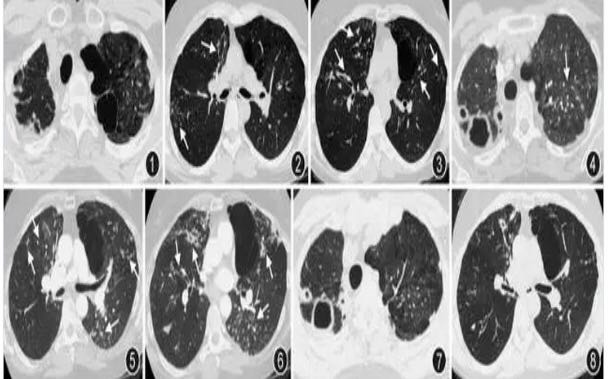

图1~3 2005年12月6日胸部CT平扫肺窗显示双上肺胸膜增厚,左上叶尖段和舌段可见肺气肿和肺大疱。双肺多发小叶中心结节、树芽征和支气管扩张,以右中叶和左上叶舌段分布为著(图2,3白箭头所示) 图4~6 2015年9月12日胸部CT平扫肺窗显示右上肺新发多个薄壁空洞(图4);左肺上叶尖段、舌段、下叶背段,以及右肺中叶结节、树芽征较前明显增多,原右肺中叶部分结节发展为支气管扩张(图4~6) 图7,8 2016年2月26日胸部CT平扫肺窗显示右上肺空洞稍缩小,左上叶舌段、下叶背段和右中叶结节较前有所吸收 辅助检查:血常规示白细胞4.62×109/L,血红蛋白96 g/L,血小板298×109/L,嗜酸粒细胞分类为0.015。尿、便常规正常。ESR为52 mm/1 h。肝肾功能、心肌酶正常。血清HIV抗体阴性。血清抗核抗体、抗中性粒细胞胞质抗体均阴性。血清肺癌标志物均正常。曲霉特异性免疫球蛋白E(IgE)水平正常。血清免疫球蛋白(IgG、IgM、IgE)水平均正常。结核感染T细胞斑点试验(T-SPOT-TB)、1,3-β-D-葡聚糖(G试验)和曲霉半乳甘露聚糖抗原(GM试验)均正常。痰涂片抗酸染色阳性,痰涂片找真菌阴性,痰培养阴性。行支气管镜检查,各级气道正常,右中叶行肺泡灌洗,送检BALF涂片抗酸染色阳性,BALF培养为鸟分枝杆菌复合群(Mycobacterium avium complex,MAC)。

最终诊断为非结核分枝杆菌(鸟分枝杆菌复合群)肺病。给予口服克拉霉素(100 mg/d)、利福平(450 mg/d)、乙胺丁醇(600 mg/d)及链霉素(每周3次,每次50万单位),2个月后复查胸部CT,右上肺空洞稍缩小,左上叶舌段、下叶背段结节影较前有所吸收(图7,图8)。患者继续口服药物随访中。